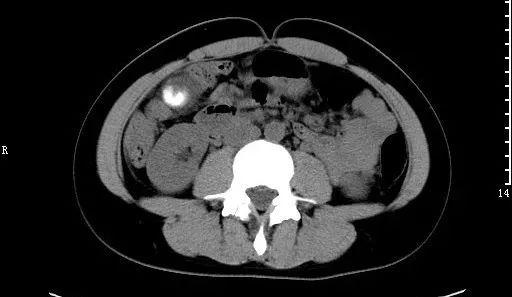

4)泌尿系结石:结石可见于肾、膀胱、输尿管和尿道的任何部位。临床表现因结石所在部位不同而有异。肾与输尿管结石的典型表现为肾绞痛与血尿,突发一侧腰部剧烈的绞痛,并向下腹及会阴部放射,伴有腹胀、恶心、呕吐、程度不同的血尿;膀胱结石主要表现是排尿困难和排尿疼痛。

X线腹平片,可以看到大部分的泌尿系结石,但对阴性结石无法显示。CT的诊断结果准确率最高,客观显示结石及积水情况。

右肾结石:腹部卧位平片可见右侧肾区结节状高密度影。

肾结石:CT平扫,右肾见不规则鹿角状高密度影,为铸型结石。

输尿管结石:CT平扫,左肾及左输尿管扩张积水,下段输尿管内可见小结节状高密度影。另见右肾小结石。